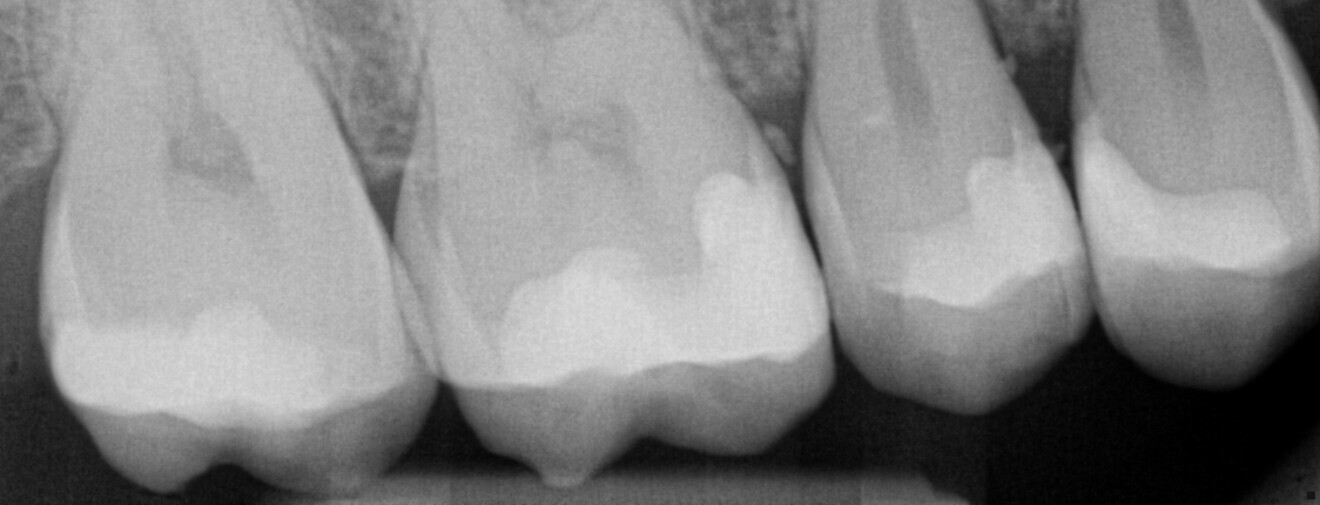

Fig. 3: Pre-op periapical radiograph demonstrating recurrent caries on the distal aspect of the maxillary right first molar.

A 46-year-old female patient presented for a recall hygiene appointment, and bitewing radiographs were taken. Proximal caries was noted on the distal aspect of the maxillary right first molar radiographically. A periapical radiograph was taken to further evaluate the tooth, and distal recurrent caries was confirmed (Fig. 3). Clinically, a chipped composite restoration on the tooth with clinical signs of composite wear on the mesial–occlusal and occlusal–palatal aspects was noted, as was distal secondary caries (Fig. 4). Removal of the failing composite and of the recurrent caries and replacement with a 3D-printed ceramic resin inlay in one appointment was recommended. The patient accepted treatment, and time in the schedule allowed treatment to be done that day.